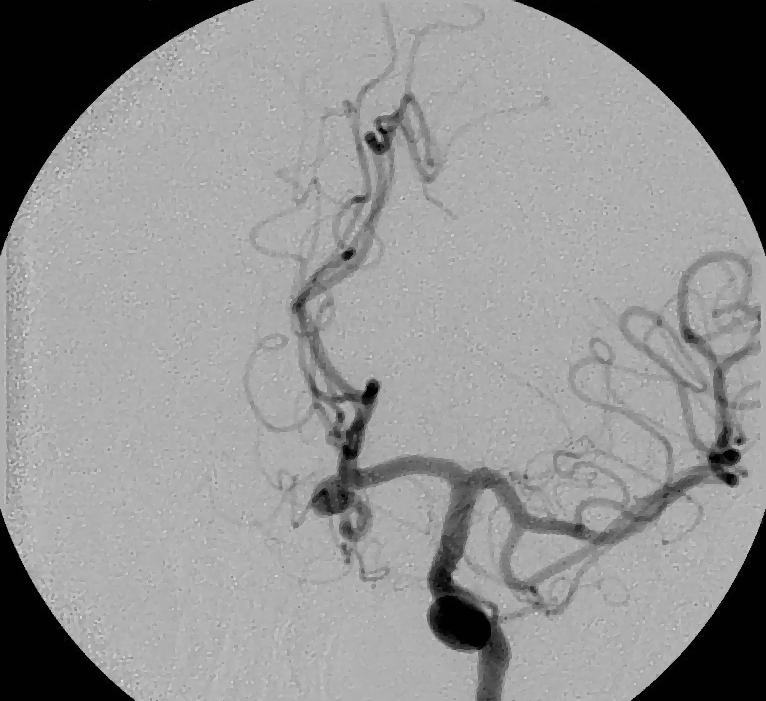

Example 2: restoration of images corrupted by blur and SPN or AWLN. In this example we evaluate the performance of the proposed TV-L1 model on three medical test images lungs (), Fig. 5 (a), ecography (), Fig. 6 (a), and aneurism (), Fig. 7 (a), synthetically corrupted by Gaussian blur of parameters band=5 and sigma=1 and by two types of impulsive noise, namely SPN and AWLN.

| (a) original | (b) TV-L1 (ISNR = 18.55) | (c) zoom of (b) |

![]() |

| (d) corrupted | (e) TVp-L1 (ISNR = 19.10) | (f) zoom of (e) |

| (g) -map () | (h) TV-L1 (ISNR = 21.14) | (i) zoom of (h) |

| (l) -map () | (m) TV-L1 (ISNR = 24.47) | (n) zoom of (m) |

First, for what concerns corruptions by SPN, in Figs. 5, 6, 7 we report for the three considered test images the original and corrupted image together with the estimated -maps in the first column (with the size of the neighborhoods used for the -maps estimation reported in the captions), the restoration results, obtained by the four compared methods, in the second column (with the achieved ISNR values in the captions) and a zoomed detail of the restored images - green- bordered in Figs. 5 (a), 6 (a), 7 (a) - in the last column.

The reported ISNR values as well as the visual inspection of the restored images and of the zoomed details strongly indicate how the proposed space-variant regularizer allows for higher quality restorations. In particular, it is worth remarking how, with respect to the space-variant TV model, the additional degrees of freedom represented by the scale parameters used in our proposal, yield a sufficient additional flexibility for avoiding unwanted spurious effects - see, e.g., spikes in Figs. 5 (i), 6 (i), 7 (i).